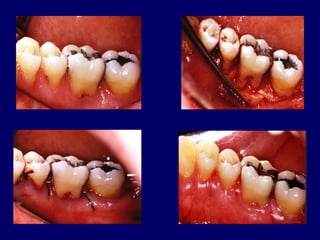

Hemisection

 Hemisection is the spiliting of a 2 rooted tooth

into 2 separate portions .

 Also called as bicuspidisation or seperation.

 Most likely to be performed on mandibular

molars with buccal and lingual classII or

classIII furcation involvement.

 After sectioning of the teeth one or both

roots can be retained .

 Narrow interradicular zones can

complicate the surgical procedure .

 Grade III furcation

– Permits plaque removal

– Root caries (4% stannous

fluoride)

– 25% failure rate at 5 years

– Recurrent periodontitis